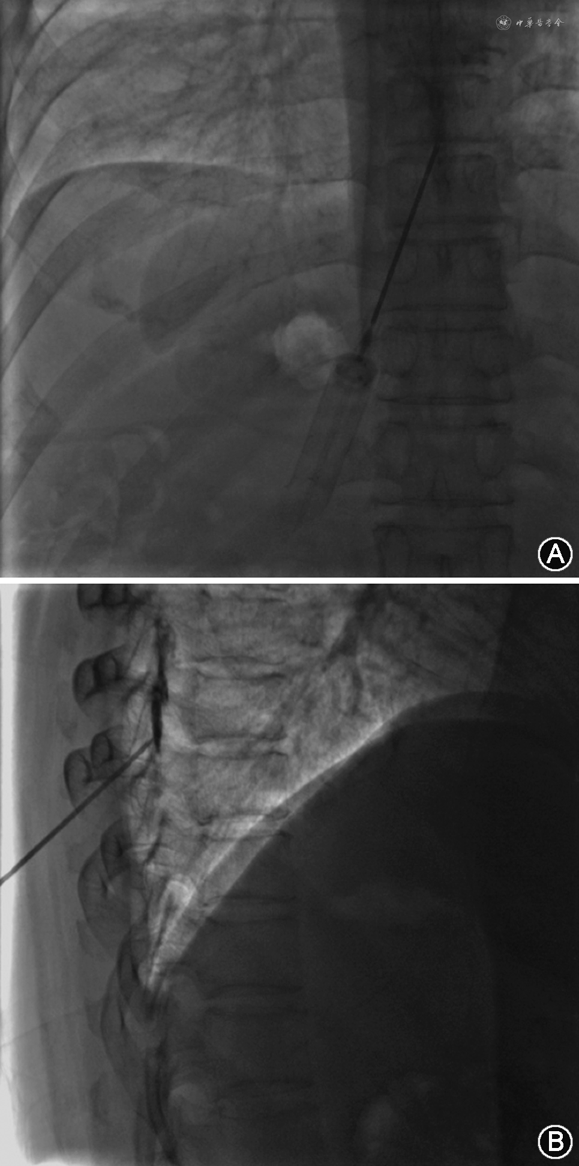

1.靶向EBP:(1)定义:靶向EBP是指根据漏口位置,以相应漏口节段为靶点进行穿刺注射的方法。术前根据影像学结果评估漏点位置,决定穿刺节段,如颈胸交界处、上胸段、下胸段等。穿刺节段越高,其硬膜外腔隙越小,穿刺风险越大,对于上胸段及颈胸交界段的穿刺建议在CT引导下谨慎穿刺[15, 16, 17]。(2)硬膜外腔穿刺:①穿刺部位选择:单发脑脊液漏漏口,选择尾侧1~2个椎体节段;多发脑脊液漏漏口,如超过6~8个节段,可选择 2个节段穿刺,头侧穿刺点可选择漏口区域。②穿刺操作方法:患者采取俯卧位,胸腹部垫薄枕,常规消毒,铺无菌巾,建议采用后正中入路穿刺,对于硬膜外腔靶向自体血分布最为有利。首先定位上下棘突的中点,局部逐层浸润麻醉后进行穿刺,依次突破皮肤、浅筋膜、深筋膜、棘上韧带、棘间韧带、椎板间隙、黄韧带,到达硬膜外腔。应避免空气阻力测试,采用结合生理盐水阻力消失法和硬膜外腔造影技术确认穿刺进入硬膜外腔。(3)硬膜外腔造影:硬膜外腔造影可帮助判断是否进入硬膜外腔及直观评估硬膜外腔结构,避免椎旁自体血无效分布。取1 ml造影剂(碘剂与生理盐水1∶1稀释),缓慢经穿刺针推注。影像下确认造影剂沿硬膜外腔分布(沿椎管位置上下扩散,无明显局部聚集,5 min后再次拍摄图像,造影剂仍显影清楚),见图1。(4)硬膜外腔置管:如造影提示无法到达靶向漏口位置,除更换穿刺节段外,可行硬膜外腔置管,但应注意避免暴力置管损伤粘连结构导致新发脑脊液漏。(5)硬膜外腔自体血靶向注射:无菌条件下将预留的自体血混合造影剂(自体血与造影剂比例为4∶1)进行靶向注射,或单纯自体血注射做造影剂替换分布(自体血注射后,漏口部位造影剂消散)。单侧脑脊液漏切勿对侧封堵,以免漏侧硬膜外腔闭塞。腹侧脑脊液漏,务必侧位X线确认分布[6]。每个穿刺点可注射10~20 ml自体血,注意观察患者有无背痛、头痛、恶心及心率、血压变化。硬膜外腔自体血注射时一定要缓慢,避免瞬间压力过大,造成颅压、血压、心率的波动,瞬时压力过大也容易使封堵液沿漏口进入蛛网膜下腔(图2)。